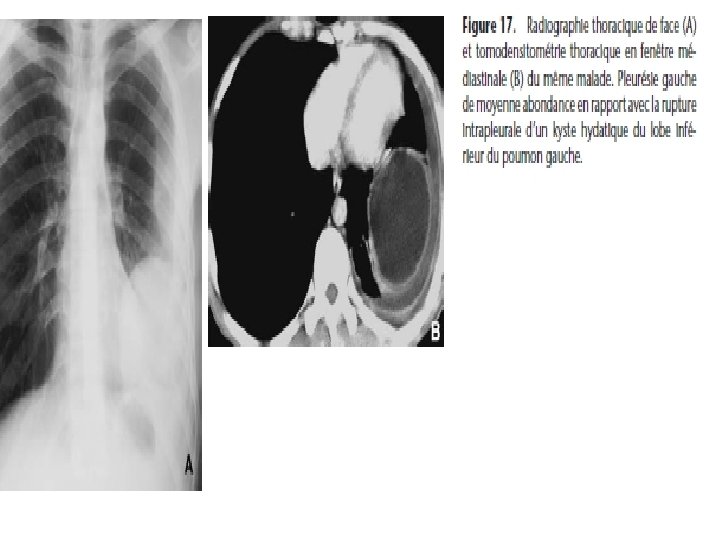

6) Rupture dans les séreuses: - hydatido-pneumothorax se transformant rapidement en hydatido-pyopneumothorax (parfois choc pleural et choc anaphylactique) RX= épanchement mixte liquidien et aérien, avec un niveau liquide généralement ondulé par les vésicules filles qui surnagent à la surface du liquide - Kyste hydatique rompu dans la cavité péricardique (mort brutale par choc anaphylactique et par tamponade)

Kystes hydatiques multiples • Infestation itérative : opacités de dimension variée • Hydatidose secondaire: rupture d’un kyste hydatique préexistant (cycle court) RX= kyste primitif rompu et kystes secondaires en nombre varié et de dimensions variées Rupture du KH du foie dans la VC ou du KH du myocarde dans le cœur droit entraine une « miliaire » hydatique qui évolue inexorablement vers la mort